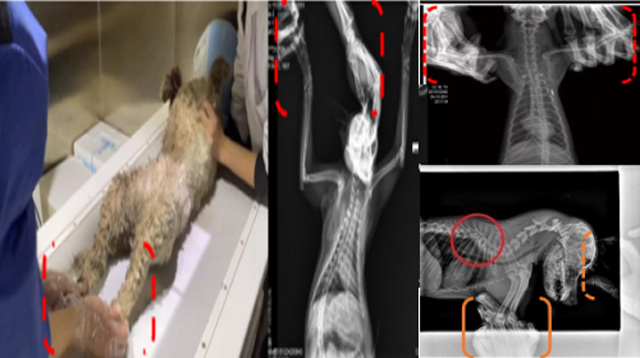

現(xiàn)在寵物醫(yī)療設(shè)備得到高速發(fā)展,現(xiàn)在有越來越多的寵物診療機(jī)構(gòu)配置X射線裝置如寵物DR。寵物骨折或者有其他疾病不能通過直觀看出來的。寵物診所醫(yī)生都會(huì)使用寵物DR來做輔助檢查。但是有時(shí)候?qū)櫸镝t(yī)生沒有加強(qiáng)防護(hù),就在寵物DR室給寵物拍X片做檢查。這樣也是會(huì)受到X射線的輻射。因?yàn)閄射線上崗是屬于職業(yè)病危害崗位。長期的輻射會(huì)對人體造成一定的危害。寵物醫(yī)生也需要接受X射線照射的上崗前都必須進(jìn)行放射工作人員的職業(yè)健康體檢。體檢不合格的話是不能擔(dān)任放射工作的。未經(jīng)上崗前職業(yè)健康體檢的勞動(dòng)者從事接觸職業(yè)病危害作業(yè)的行為,已經(jīng)違反了《中華人民共和國職業(yè)病防治法》第三十五條規(guī)定,依據(jù)《中華人民共和國職業(yè)病防治法》第七十五條規(guī)定,需要進(jìn)行整改罰款。開展寵物放射診療活動(dòng),在日常工作中,對本機(jī)構(gòu)的X射線危害的職業(yè)病防治,需要知道并做到以下內(nèi)容: